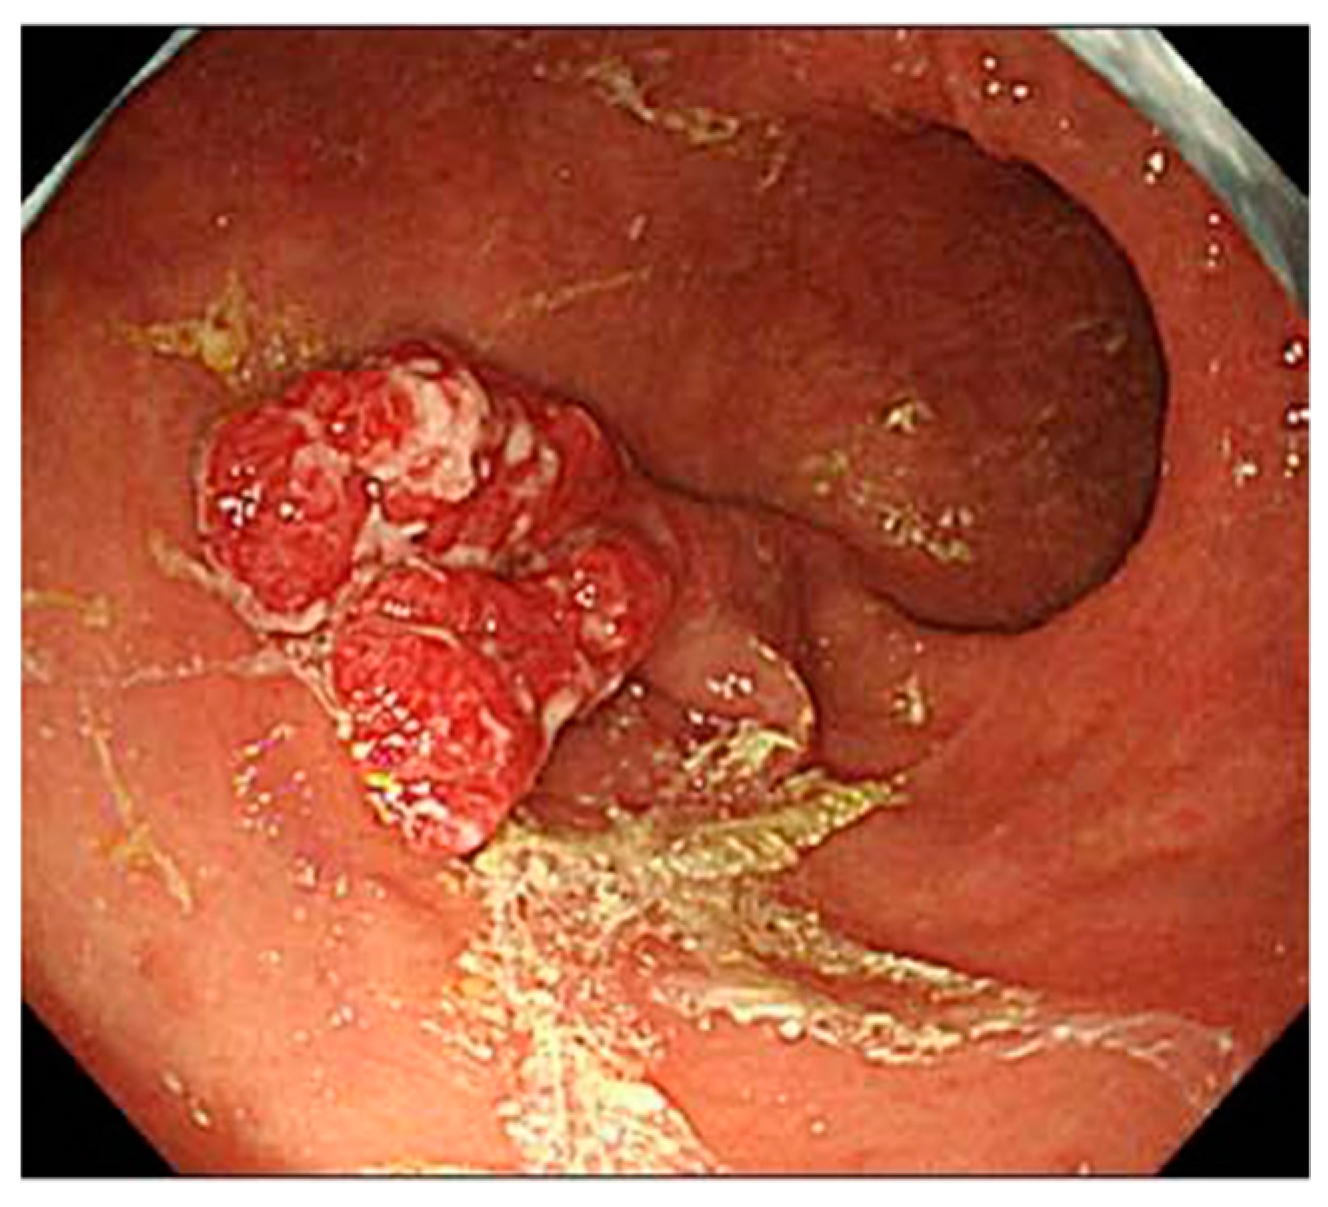

5. Findings of Early AIG

- Kotera, T.; Oe, K.; Kushima, R.; Haruma, K. Multiple Pseudopolyps Presenting as Reddish Nodules Are a Characteristic Endoscopic Finding in Patients with Early-stage Autoimmune Gastritis. Intern. Med. 2020, 59, 2995–3000. [Google Scholar] [CrossRef]